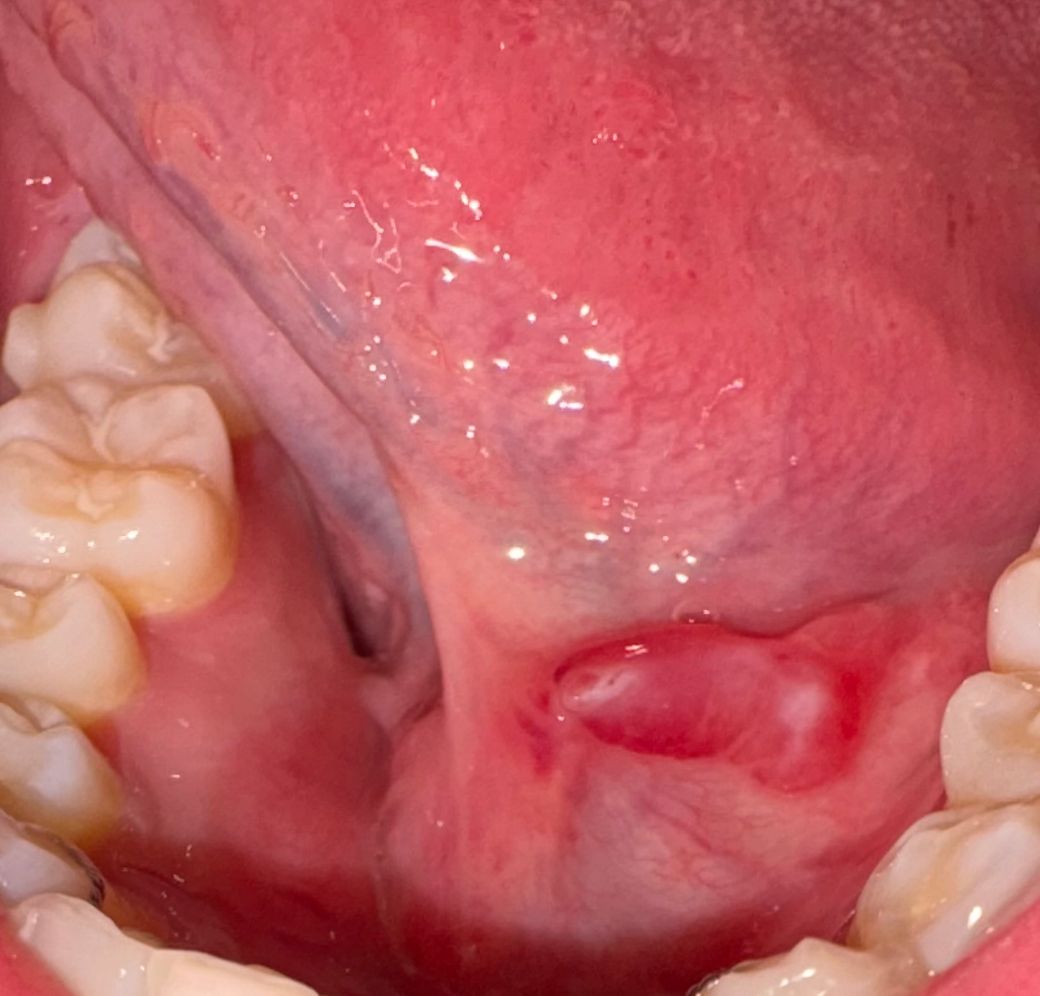

입안에 이상한 염증? 같은게 생겼어요

입안에 이상한 염증같은게 거의 2~3주동안 저렇게 났어요 혀로 건드려도 아프지도 않아요 혹시 무슨 이유때문인지 병원에 방문해야하는건지 궁금합니다

혀밑에 자극을 받아서 부종이 생긴거 같습니다. 최대한 자극이 가지 않도록 해주시고 자극적인 음식등은 당분간 피해주세요.